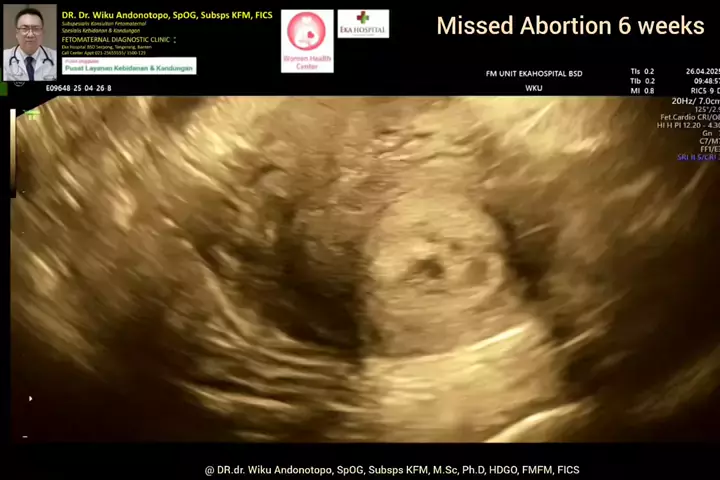

Missed Abortion 6 weeks... #drwikuandonotopo #drwiku_andonotopo #polikandunganekahospitalbsd #fetomaternalekahospitalbsd #usgfetomaternalekahospitalbsd #konsultanfetomaternalekahospitalbsd #ekahospitalbsd #ekahospitalcibubur #ekahospitalbekasi #ekahospitalpekanbaru #fetomaternalbekasi #fetomaternalcibubur #fetomaternal #konsultanfetomaternal #usg #usg4d #perkembanganbayi #perkembanganjanin # #melahirkannyaman #melahirkannormal #melahirkancesar #janin #lahiran #melahirkan #melahirkansc #melah...